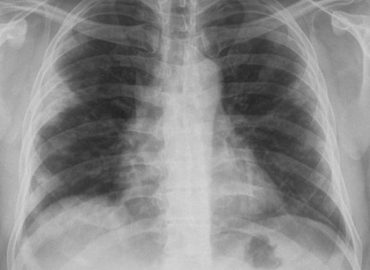

Paciente masculino de 40 años. Consulta por Fiebre y Disnea de una semana de evolución. Sin respuesta a antibióticoterapia.

Femenina 64 años Motivo de Consulta: Tos y equivalentes febriles